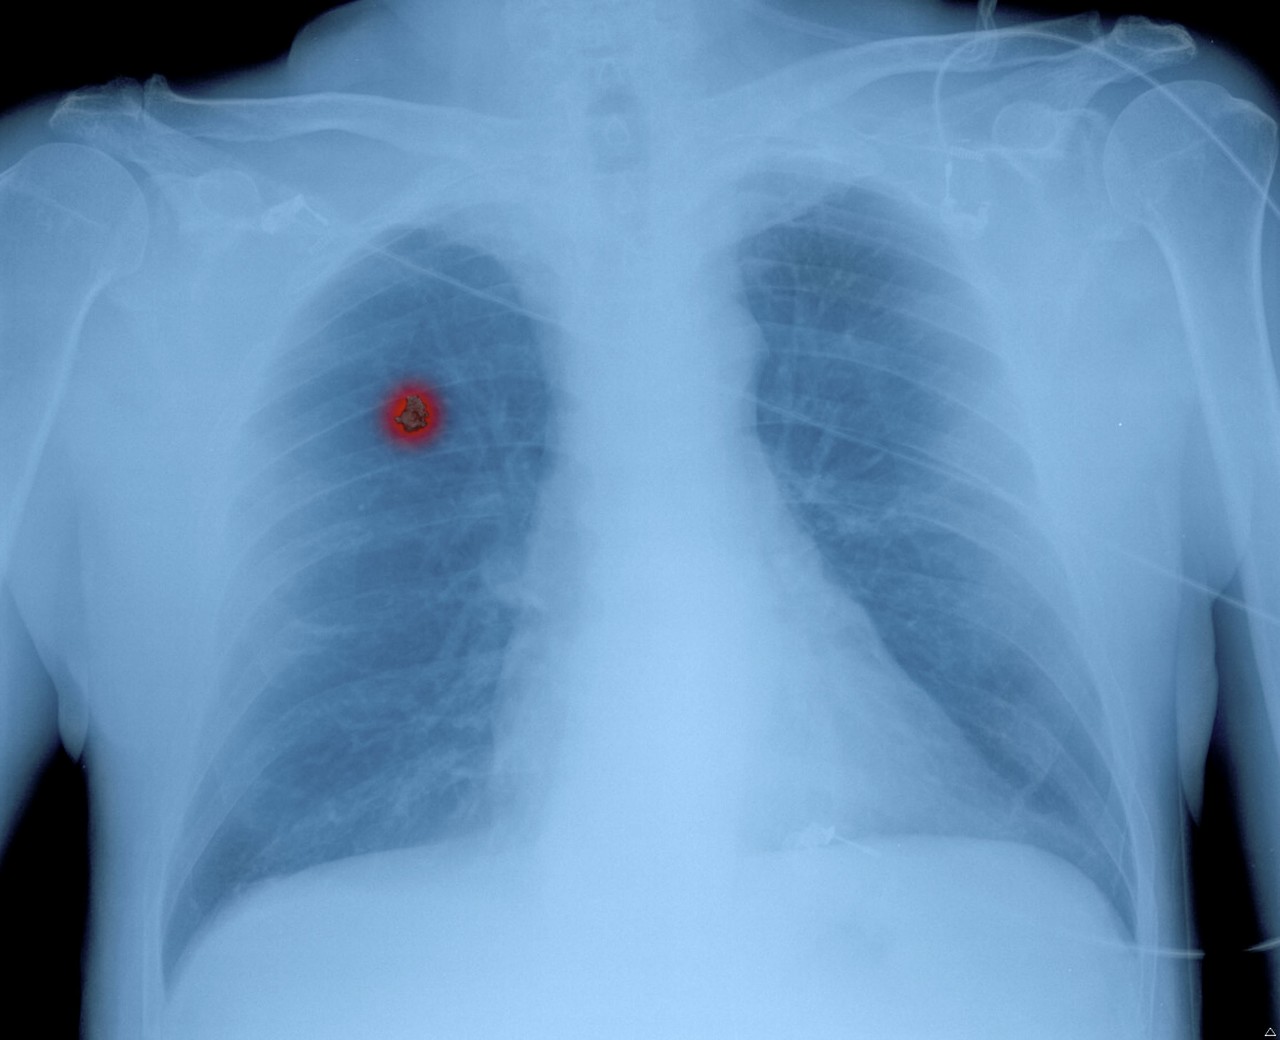

肺がん